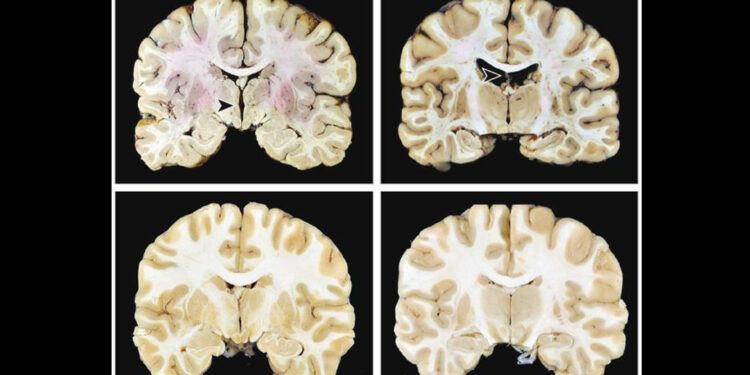

(MedPage Today) — Higher stages of chronic traumatic encephalopathy (CTE), a disorder associated with repetitive head impacts often from contact sports like American football, were tied to increased odds of dementia, autopsy data showed.